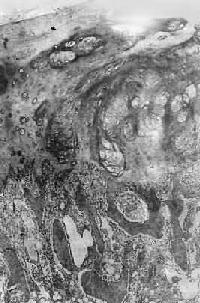

图17-7 硬化性骨肉瘤 股骨干骺端呈梭形肿大,骨干被包埋于中央,周围有清晰的放射状骨梁 骨肉瘤的切面呈多彩状,其外观取决于肿瘤性骨质及软骨的含量以及出血、坏死等继发改变的程度。例如,肿瘤性骨质成分较多时则肉眼观呈黄白色,质地坚硬,有砂粒小点或条纹;如软骨形成明显时则呈半透明状;在肿瘤细胞丰富部位则呈灰红色鱼肉状。 镜下,骨肉瘤由明显间变的梭形或多边形肉瘤细胞组成,细胞大小不等,核形奇异,大而深染,核仁明显,易见病理性核分裂像。肿瘤细胞直接形成肿瘤性类骨组织或骨组织,是诊断骨肉瘤的最重要的组织学依据。所形成的类骨组织或骨组织在不同肿瘤或同一肿瘤的不同部位多少不等。往往可看到肿瘤性骨质发生过程中各阶段的形态,最早期在恶性肿瘤细胞间出现均质红染的胶原样物质,其后红染物质逐渐增多,将肿瘤细胞分隔疏远,构成小梁或片状的肿瘤性类骨组织(图17-8)。类骨组织可伴钙盐沉着,其内的肿瘤细胞固缩变小,形成肿瘤性骨质。骨肉瘤内也可出现肿瘤性软骨(图17-9)。

图17-8 骨肉瘤

图17-9 骨肉瘤 骨肉瘤起源于间叶细胞,形态上表现出多方向分化的潜能,而使骨肉瘤的成分较为复杂。根据其主要的分化成分,组织学上可分成几种类型:最常见者为骨母细胞型,以异型骨母细胞为主要成分,细胞呈多边形,较肥硕,核圆、核仁明显,胞浆丰富,伴较多的肿瘤性类骨和骨组织形成;由软骨肉瘤样组织为主要成分者,属软骨母细胞型;以梭形细胞和胶原纤维为主,似纤维肉瘤者为纤维母细胞型;肿瘤内有许多显著扩张的血管腔隙,伴较多破骨细胞型多核巨细胞,甚似动脉瘤性骨囊肿者为血管扩张型,此型十分少见。在同一肿瘤中上述各种类型的成分常混合存在,但以某一类型为主。不论何种类型,都能见到肿瘤细胞直接形成肿瘤性类骨和骨组织,这是区别于其他骨肿瘤的特征。 【临床病理联系】 骨肉瘤最早的症状是局部疼痛,日渐加剧,持续不断,以夜间为明显。发病2~3月后,局部出现肿胀、质地坚硬。患部皮肤紧张,多呈紫铜色,表面静脉曲张。如骨皮质受侵犯时,轻度外伤即可致病理性骨折。 血清碱性磷酸酶的增高是骨肉瘤的唯一重要化验室检查指征,这和瘤组织内碱性磷酸酶的含量增高相一致,约见于半数病例,对骨肉瘤诊断和推测预后有一定价值。 X线检查对骨肉瘤的诊断有重要价值。常见到肿瘤性骨质形成,表现为云絮状或斑块状密度增高的阴影。这类病例在X线诊断时称为硬化型骨肉瘤。少数病例呈溶骨型,病理上主要为软骨母细胞型和纤维母细胞型以骨质破坏为主,呈虫蚀状或大片状骨质破坏,边界模糊。如前所述,X线检查如发现Codman三角或日光放射状阴影,则对骨肉瘤的诊断很有帮助。 骨肉瘤是高度恶性肿瘤,一般生长迅速,预后较差。局部扩展一方面侵犯骨髓腔及骨皮质,并破坏骨膜及周围软组织;另一方面向骨骺蔓延,甚至扩展到关节软骨。极少数病例可越过关节软骨,侵入关节囊,造成关节活动障碍。近年还发现,骨肉瘤在骨内可呈跳跃性转移(skip metastasis),即在与原发瘤同一骨内的另一处形成孤立性转移结节,甚至还可以转移到相邻的骨内,形成孤立结节,约见于1/4的病例,且不易被X线检查发现,因而预后更差。远处转移多经血道到肺,不少病例在发现原发瘤的同时,即已有肺转移。极少数病例可转移到局部淋巴结。 皮质旁骨肉瘤是骨肉瘤的一种特殊亚型。与一般骨肉瘤不同,本瘤发生于骨膜或骨旁的成骨性纤维组织,瘤体的主要部分位于骨的表面。大多生长缓慢,恶性程度较低,预后远较一般骨肉瘤好,其发病年龄比一般骨肉瘤大5~10岁。本瘤好发于股骨下端的后方,其次为股骨上部。瘤体一般较大,边界较清晰,可呈分叶状。早期对骨质侵犯较少,故易于剥离;晚期可破坏骨皮质而侵犯骨髓腔,但远处转移少见。在切面上,靠近骨皮质或骨膜部分质坚实,而瘤体边缘部分较软,为富于瘤细胞部分。瘤体一般不见出血及坏死。镜下,为分化好的骨肉瘤,成骨现象比较明显。在肿瘤性骨小梁间为增生较活跃的纤维组织,间变不明显,形态上似分化好的纤维肉瘤。少数皮质骨肉瘤分化较差,形成骨质较少,与骨内骨肉瘤相似。